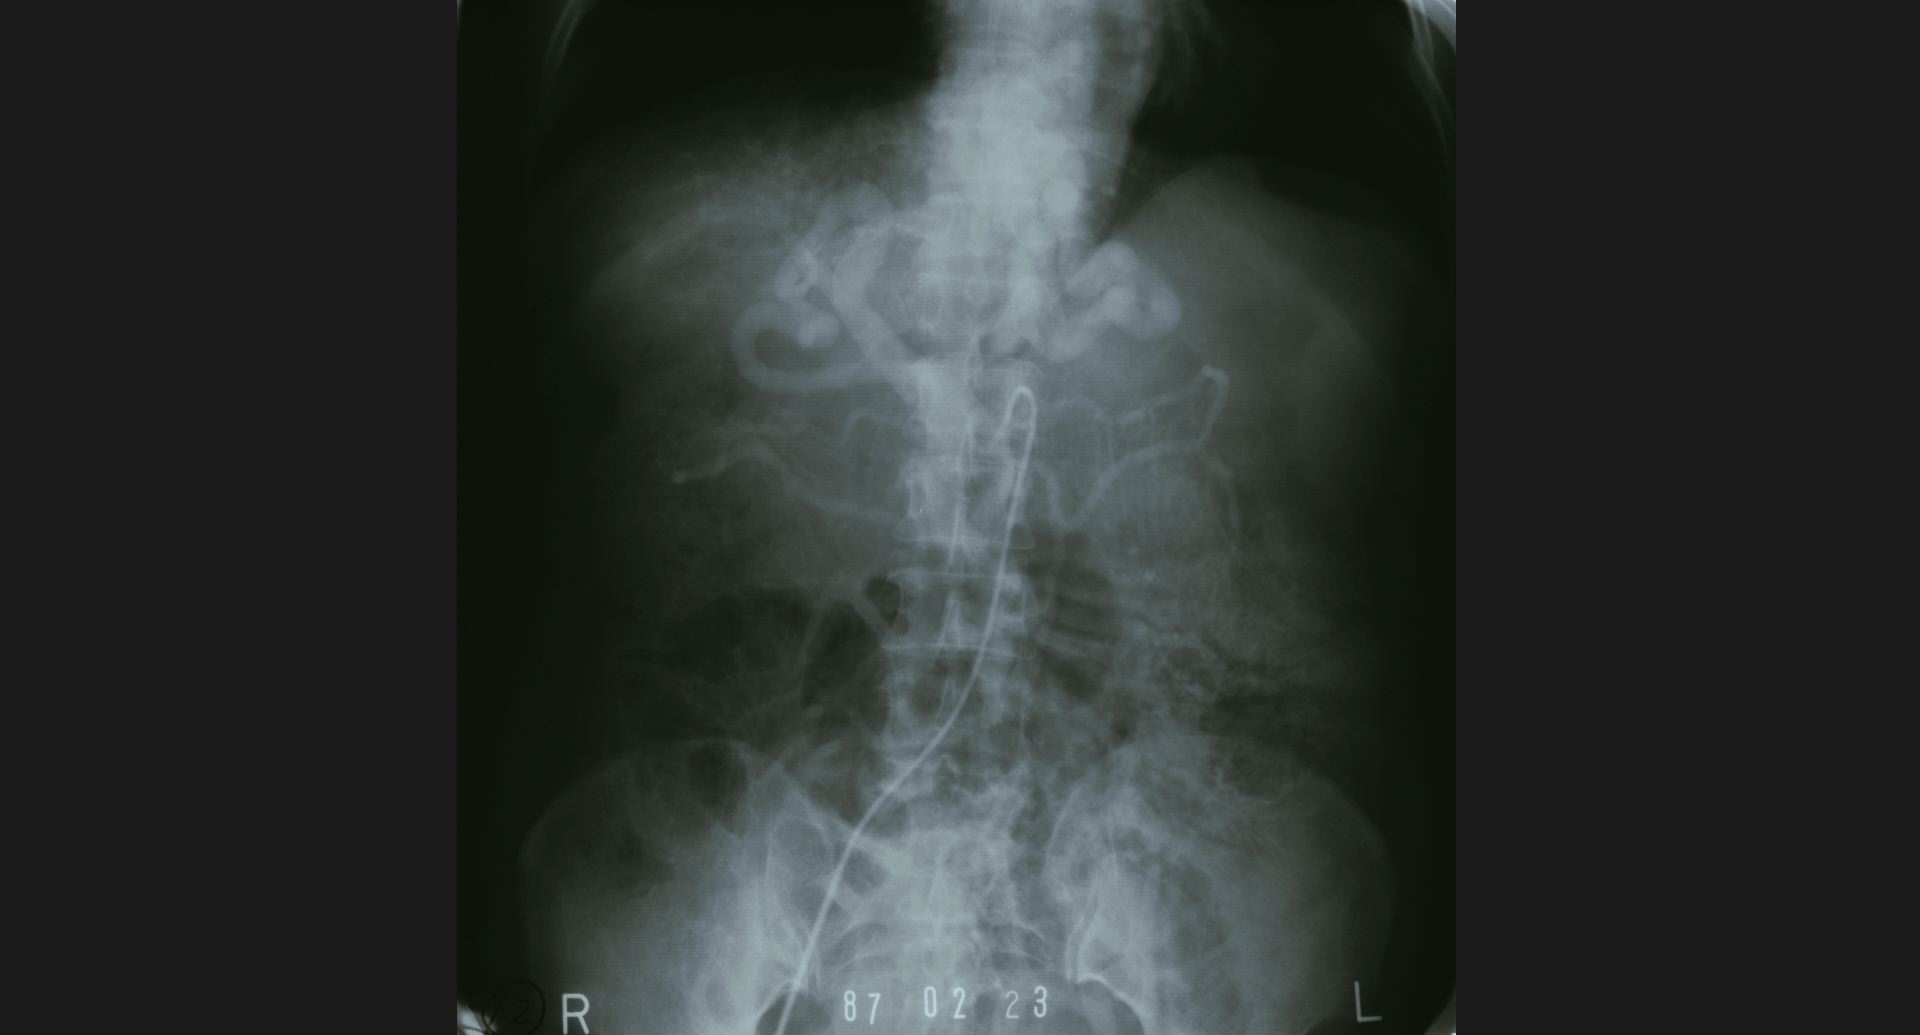

fig.10(99KB)

:SMA thrombosis (angiography)閉塞部位。腸管壁の細かい動脈。